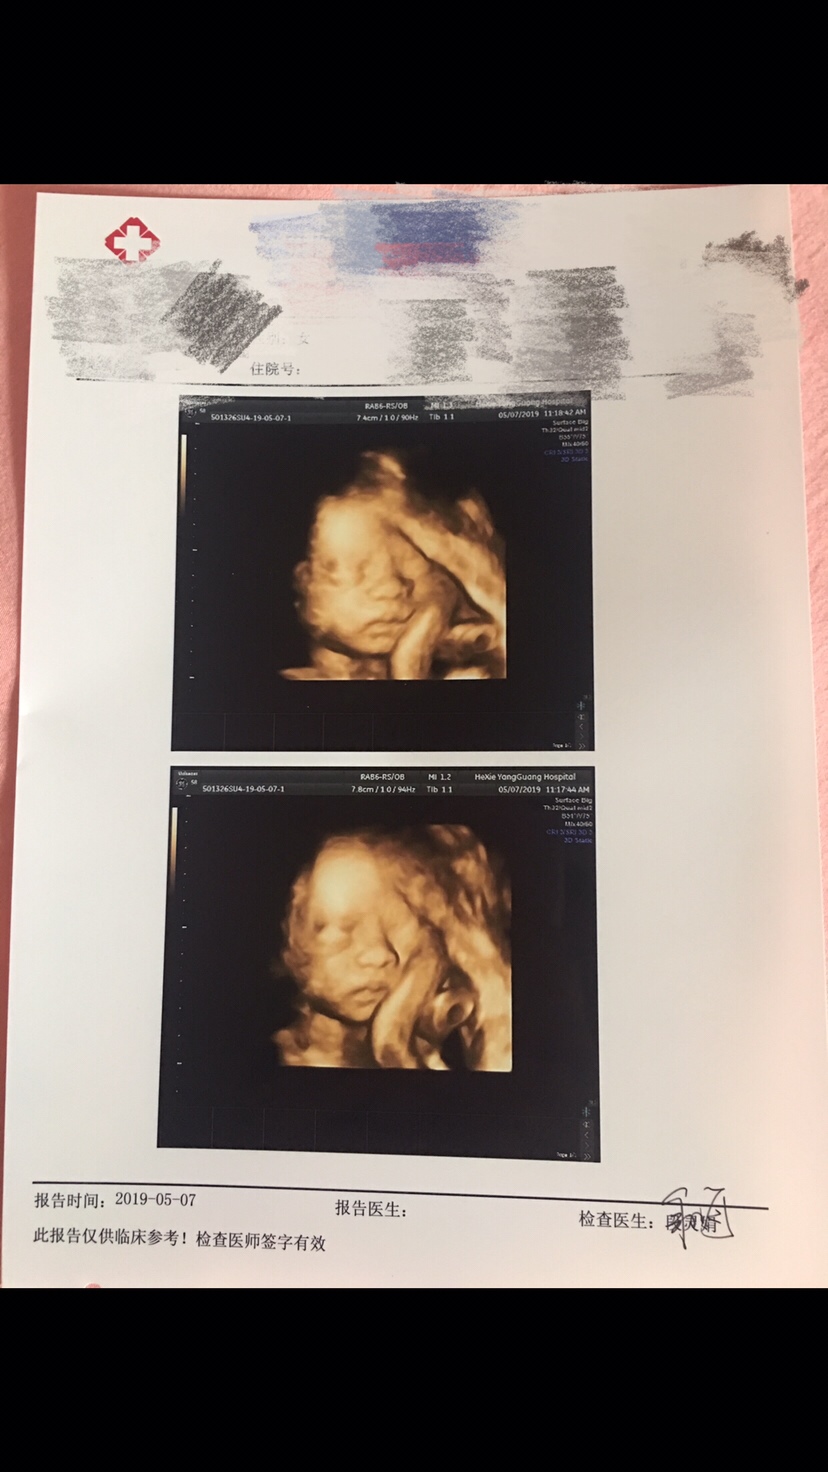

孕32周+3天

80%是小王子